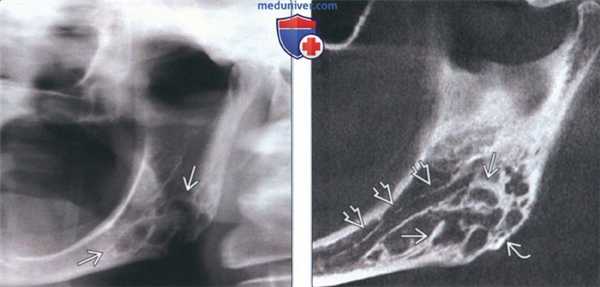

(Слева) На панорамной рентгенограмме определяется десмопластическая фиброма в виде многокамерного просветления в задних отделах нижней челюсти слева и в области угла. Отношение нижнечелюстного канала к опухоли неясно.

(Справа) На панорамной реформатированной КЛКТ у этого же пациента определяются толстые перегородки в опухоли, распространяющейся в нижнюю кортикальную пластинку. Отчетливо визуализируется смещенный кверху нижнечелюстной канал. Расположение опухоли под нижнечелюстным каналом позволяет исключить одонтогенное поражение.

(Слева) На корональной КЛКТ у этого же пациента определяется многокамерное образование, не приводящее к вздутию. Не исключается эрозия щечной кортикальной пластинки в нижних отделах. При подозрении на вовлечение мягких тканей методом выбора является MPT.

(Справа) На панорамной рентгенограмме у этого же пациента, выполненной после операции, определяются признаки заживления кости с наличием стабилизирующей пластины. В случае таких агрессивных опухолей с целью недопущения рецидива рекомендуется резекция или широкое иссечение.